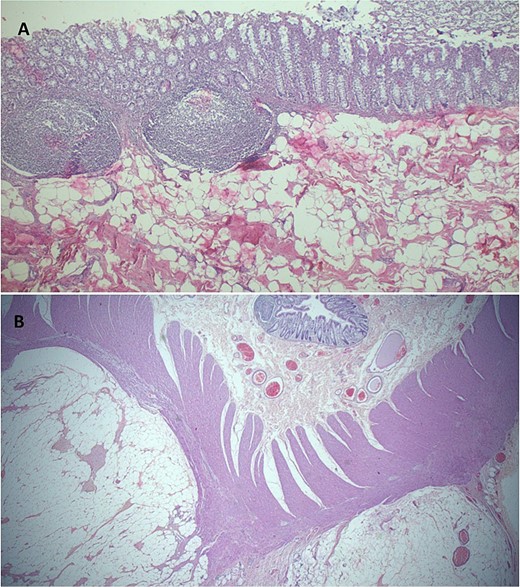

Her postoperative recovery was uneventful, and she was discharged on Day 6. At her 4-week follow-up, no complications were noted. Histology revealed a lipomatous tumor located 10 cm from the distal resection margin, encroaching the muscularis propria without evidence of cytological atypia (Fig. 2).

(A) Histopathology demonstrating normal colonic mucosa, submucosa demonstrates a mesenchymal lesion comprised of matured fat cells (H&E staining at 40× original magnification). (B) Photomicroscopy highlighting a benign, well circumscribed colonic lipomatous tumor dissecting muscularis propria muscles (H&E staining at 20× original magnification).